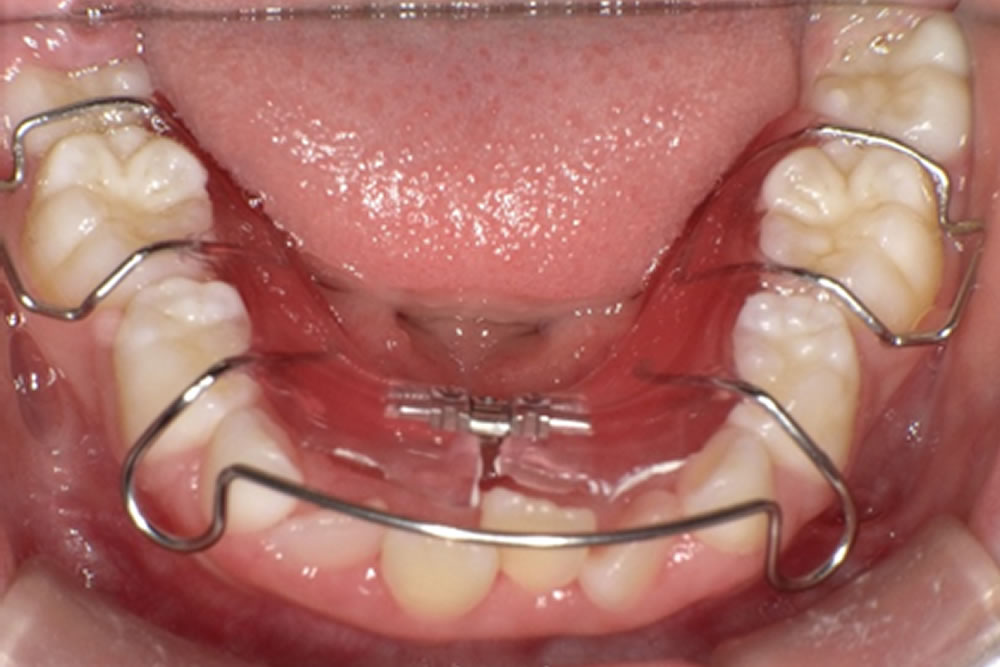

こちらの患者さまは歯並びが気になるとのことでご来院されました。

歯が並ぶスペースを確保するため、成長を促す装置を使用する「床矯正」を始めることになりました。

矯正を始める前の口腔内の状態です。下の前歯が生え変わる際にスペースが不足しているため、歯が斜めに生えてきていることが分かります。

各種検査・レントゲン撮影・口腔内写真の撮影・模型の作製などを行い、治療計画を立案します。

床矯正の開始

上の前歯も順調に生え変わりが進んでいますが、スペースが不足しているため、下顎と同様に装置を作製・装着しました。

その後は約2年間、3カ月に1回のペースでクリーニングを行いながら装置の状態をチェックしていきます。必要に応じて、その都度調整も行います。

途中経過の写真です。上下どちらも歯が綺麗に並んできました。さらに調節を行っていきます。

さらに期間が経過し、歯並びの状態を確認した写真です。前回の写真と比べると、下顎では乳歯が抜け、4番目の永久歯が生えてきていることが分かります。また、1番目の歯同士もきれいに並び、歯列が整ってきました。上顎では、2番目の永久歯がきれいに歯列に並んできています。

治療完了

最終的な口腔内の状態です。途中経過と比べても、歯並びがさらに改善されたことが分かります。装置は後戻りを防ぐため、リテーナーとして継続して使用していただきますが、乳歯がすべて抜けて永久歯への生え変わりが完了した時点で終了となります。

こちらの患者さまは生え変わりが完了し、矯正治療を終了しました。現在はメンテナンスに通院しながら経過を確認しています。

残っているデコボコした部分を整えるために、必要に応じて再度細かい矯正治療を行うことも可能である旨をお伝えしましたが、現時点では治療結果にご満足いただいております。さらに歯並びを整えたい方は、成人矯正へ移行するケースもあります。